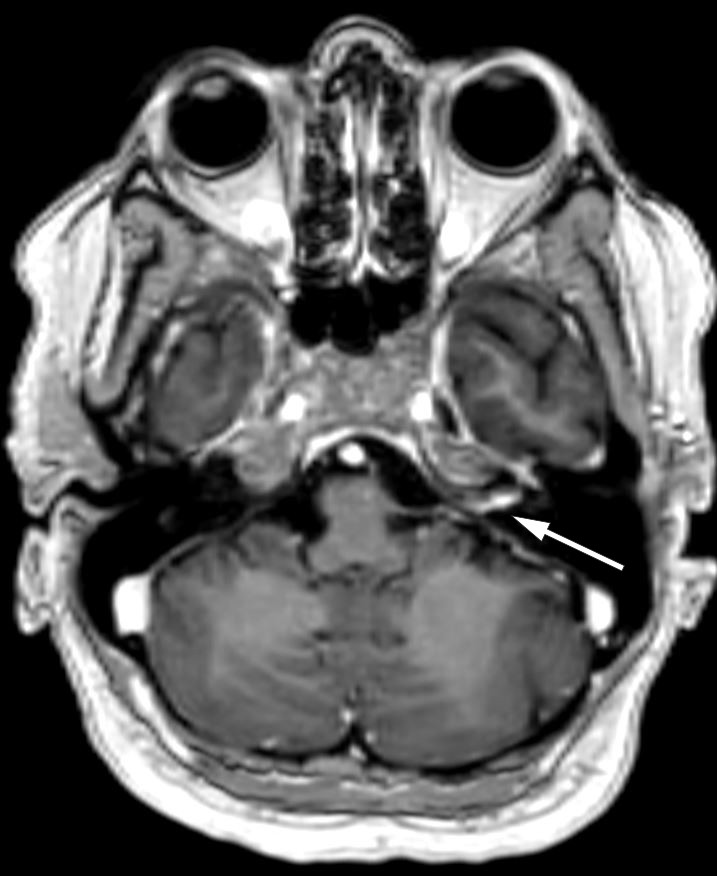

Tre dager senere ble pasienten reinnlagt grunnet forverring av svimmelhet og kvalme. Ny MR av hodet viste tegn til inflammasjon, med økt kontrastoppladning i indre øregang og langs facialisnervens tympaniske og mastoide segment på venstre side (T1-vektede bilder) (figur 2) og økt signal i indre øregang i både cochlea og vestibularisapparatet på venstre side (FLAIR SPIR-sekvenser). Videonystagmoskopi med kalorisk testing viste 56 % svakere respons på venstre side, som tegn på redusert funksjon i vestibularisnerven. Det ble bemerket et kløende, papuløst utslett i hodebunnen. Dette var en sannsynlig bivirkning av valaciklovir.